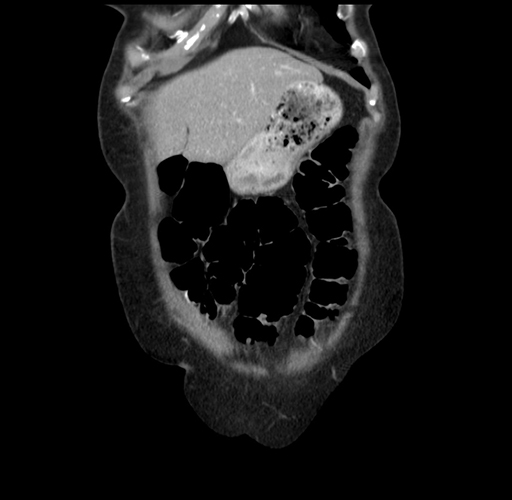

Pre-Chemo: Coronal Venous

Coronal Venous